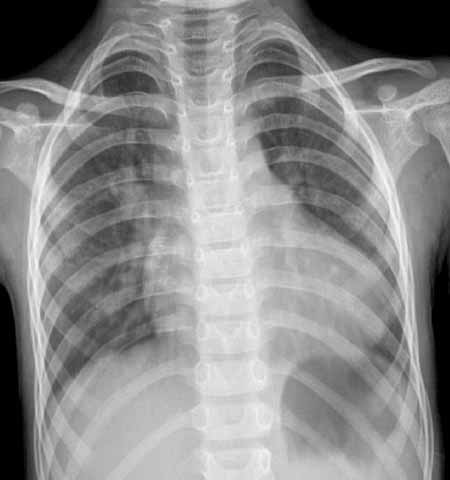

男,5岁,发现心脏杂音5年。

双肺肺血增多,心脏向左增大,以左心室增大为主,肺动脉段微凸..多考虑:多血型先心病_室缺?

左心室高度增大,肺血增多,考虑:动脉导管未闭。

两心室均增大,室缺.

左室大主动脉结节小,室缺

左房左室大,肺血增多,主动脉结无明显改变,不排除室缺可能,请结合临床。

左房左室大,肺血增多,主动脉结无明显改变,不排除动脉导管未闭可能,请结合临床。